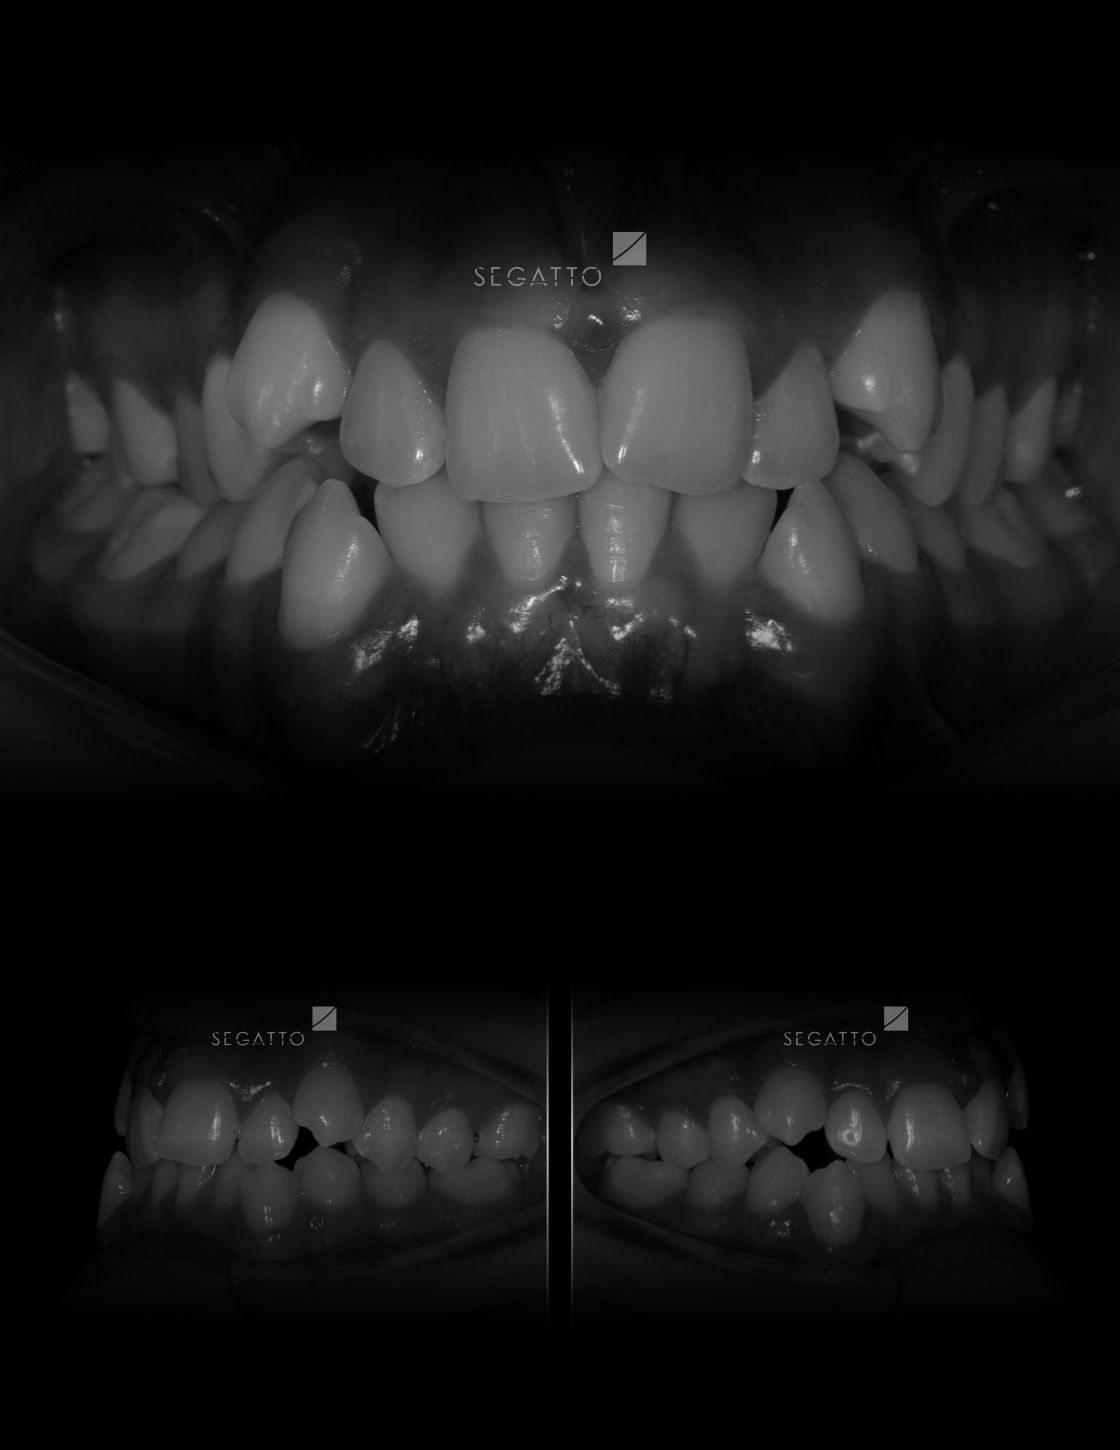

Orthodontics

Cases